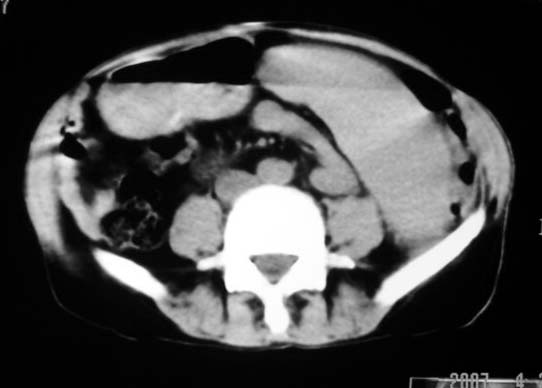

以下是引用dyqct在2007-4-20 16:38:00的发言:[br]考虑:1、巨脾;[br] 2、肝内多发低密度,首先考虑转移瘤;[br] 3、胆囊多发结石。

以下是引用andymaomao在2007-4-20 16:47:00的发言:[br]肝脾增大,肝内胆管扩张,且可见多发小囊性低密度灶,胆囊窝区高密度影,手术化疗病史,贫血....[br]1.肝脾大及贫血与术后化、药疗有关;[br]2.胆囊窝区高密度影,术后改变?肝内胆管扩张,积液?[br]3.肝内多发低密度灶,性质?建交增强